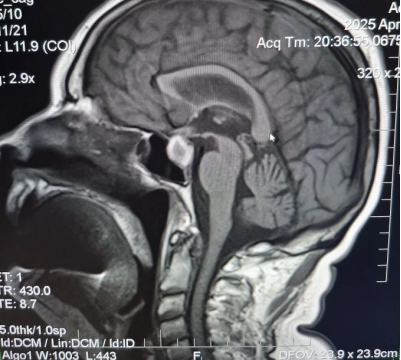

Затем, 17.12.2022, прошла МРТ головного мозга (рис. 4, рис. 5, рис. 6).

Рис. 4. МРТ головного мозга (T1 SE sag)

Рис. 5. МРТ головного мозга (T2 TSE)